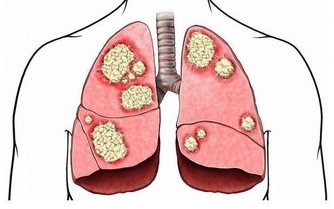

中醫認為,「肺為嬌臟」,「溫邪上受,首先犯肺」,肺是最容易受到外來有害物質侵害的臟器。

肺部有毒的表現症狀

肺毒的原因:肺毒也叫氣毒,主要和空氣品質有關,

肺毒的表現:呼吸不暢、胸悶、咳痰。

肺怕霧霾、煙氣刺激。中醫學認為,胸中為「上氣海」,丹田為「下氣海」,氣之所以能夠運行於全身,依賴肺氣的推動作用。

肺為「清虛之髒」,但霧霾、長期吸煙、二手煙不時傷害著它,

導致肺泡內痰飲積滯,阻塞氣道,清氣不能吸入,濁氣不能排出,上下氣海不流通,血液不能正常迴圈。